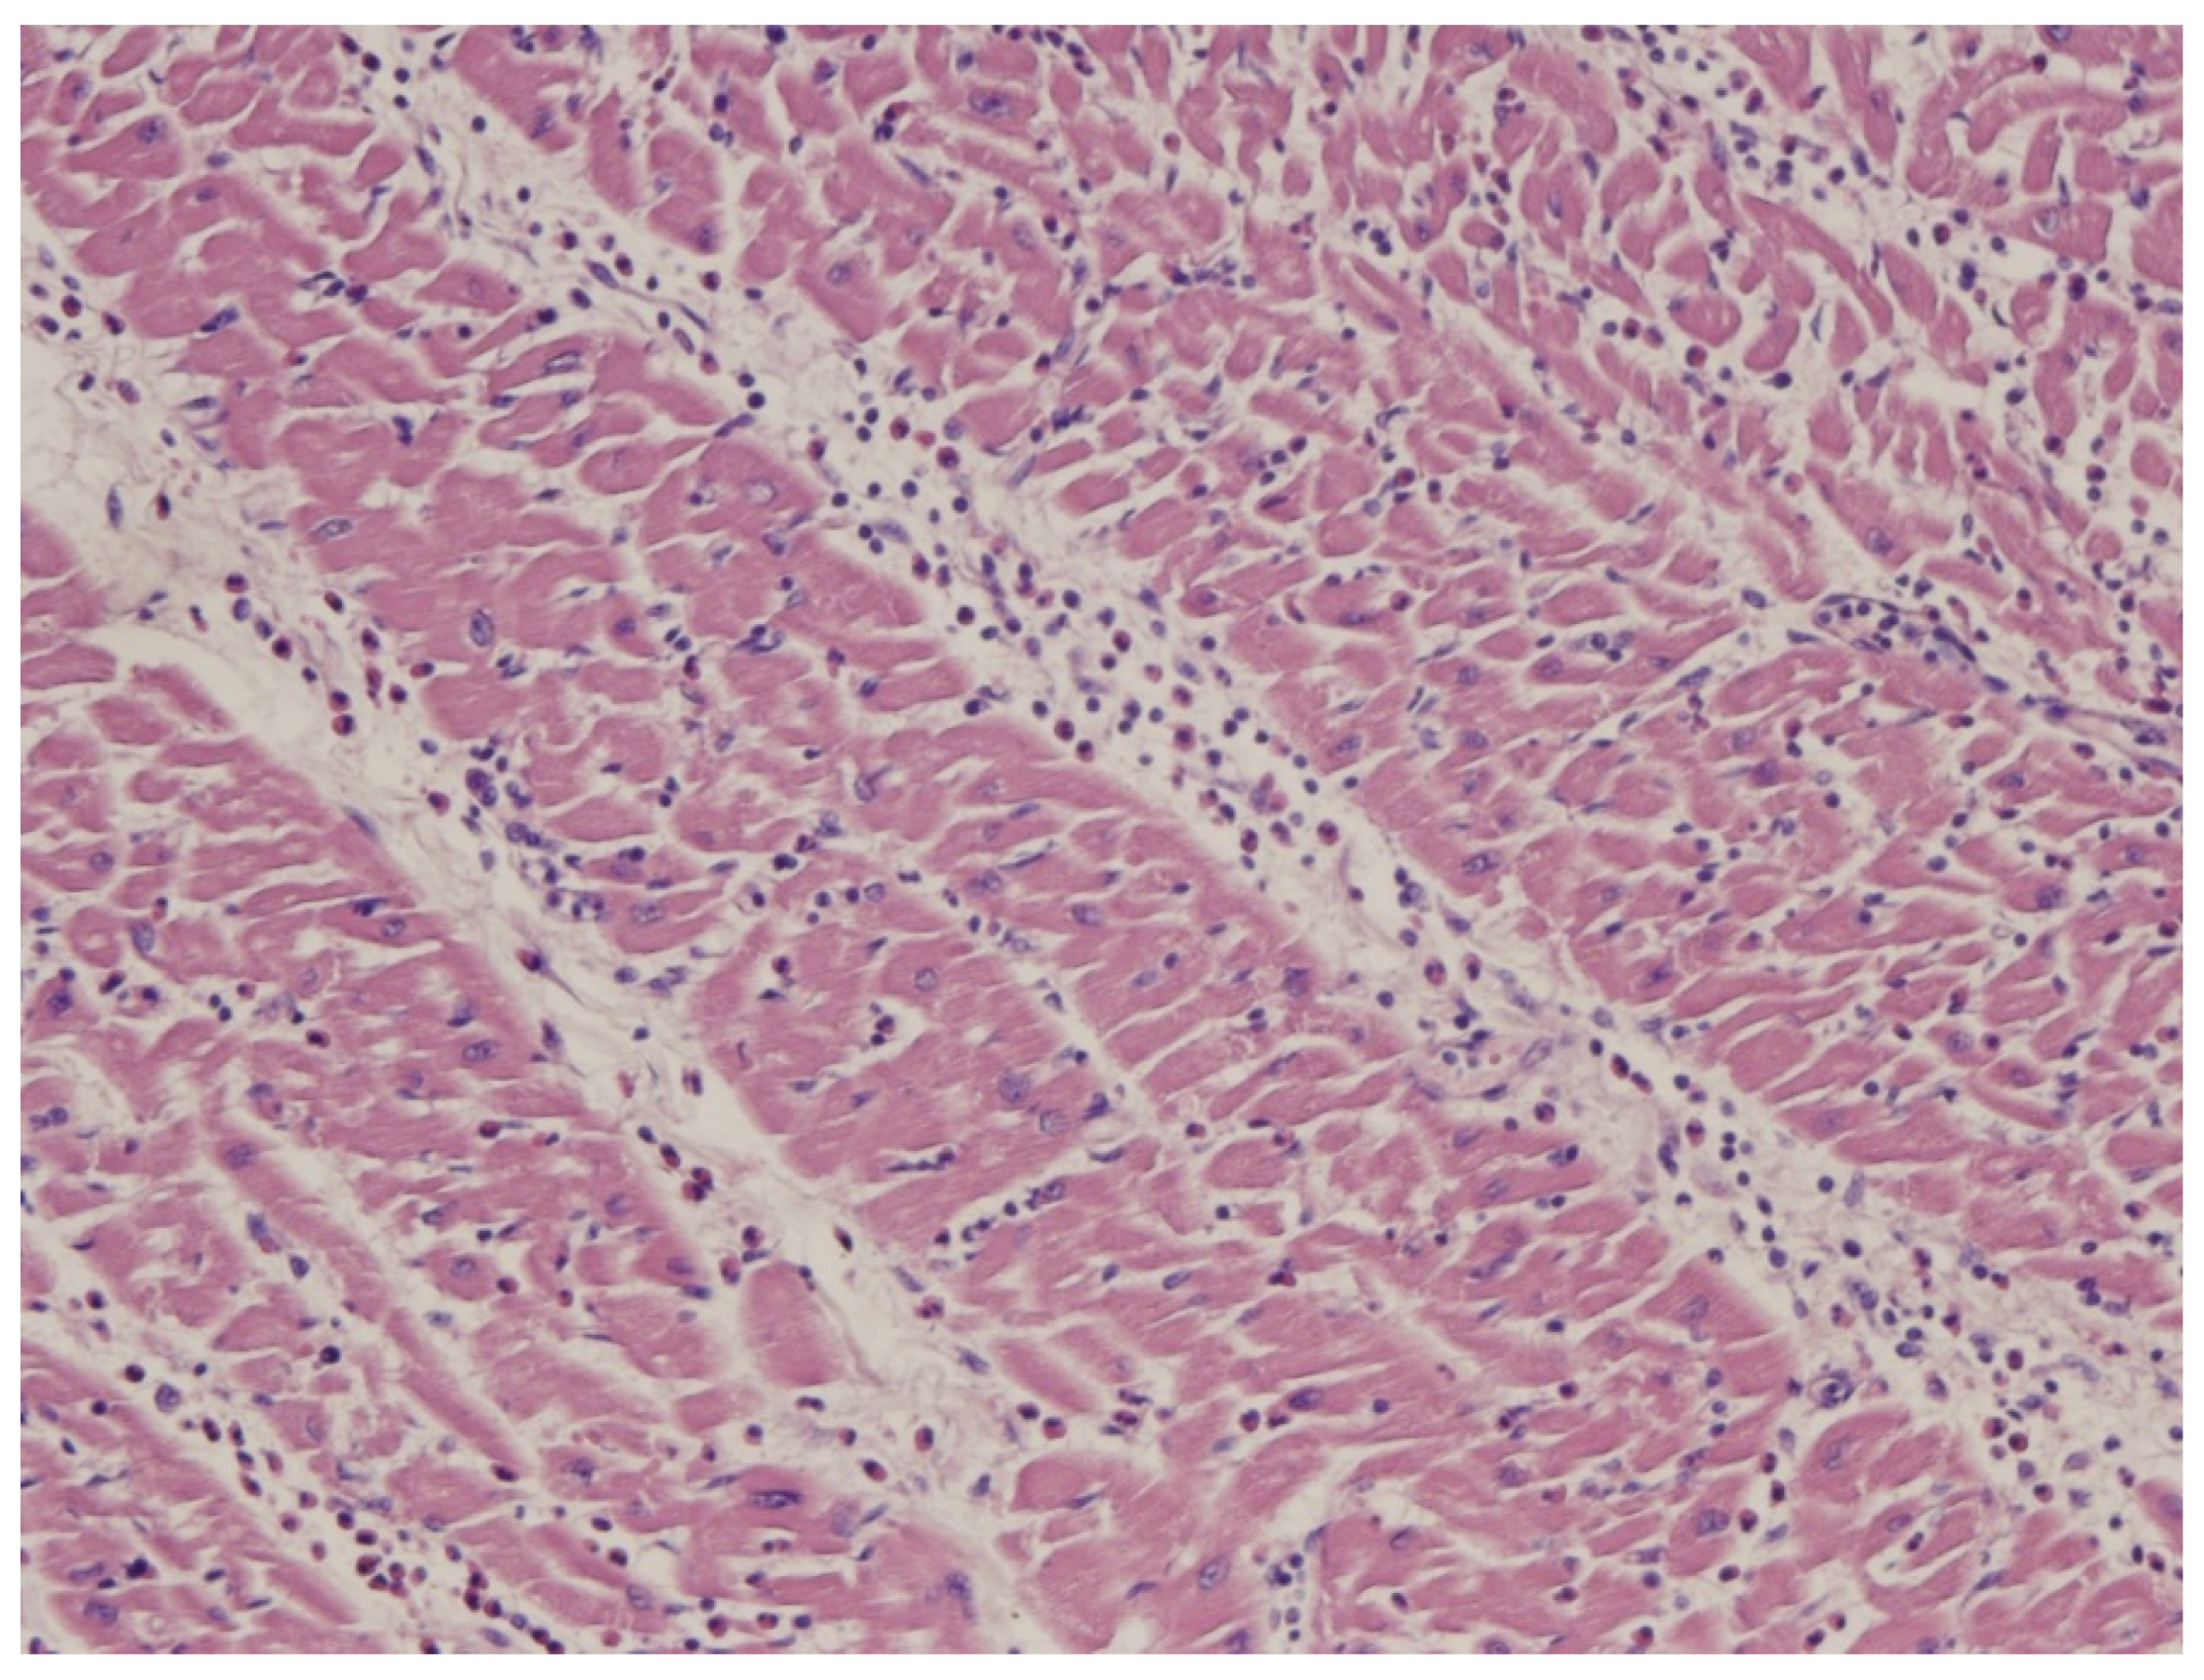

9. Diagnosis of ACM Through Endomyocardial Biopsy and Infiltrative Disease as Amyloidosis